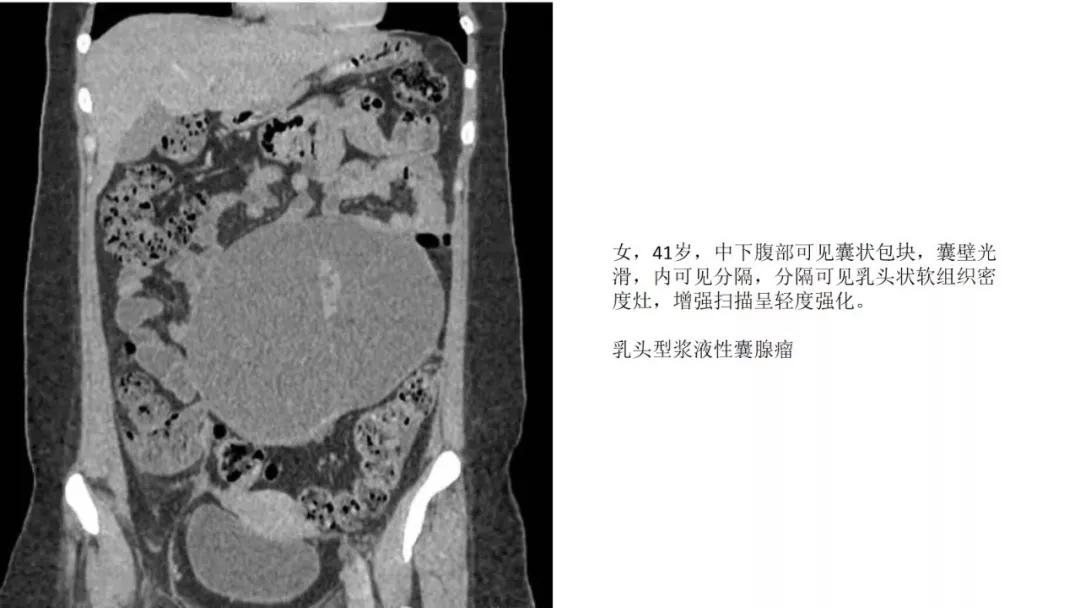

上皮性肿瘤:最常见,恶性多(卵巢癌),良性少。好发于50Y以上,发现时多为中晚期。多呈囊性或以囊性为主的囊实性肿块,完全实性者少见。形态多数不规则,边界模糊,囊壁及房间隔常不规则增厚,菜花样肿物或壁结节,囊实性区域分界不清,实性肿瘤常有不规则低密度或坏死区,可有边界模糊沙粒状或块状钙化,中-高度强化。良性者边界清晰,囊壁薄光整,无壁结节,实性部分呈无或轻度强化。

- 卵巢癌中最常见的是浆液性囊腺癌,约占1/3。